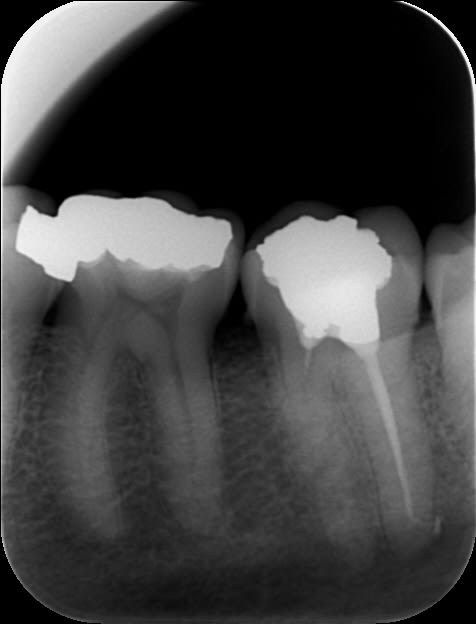

la digue...pourquoi ??

pas d'endo, pas de digue...où est le problème ??

Faut se concentrer sur "ce qui rapporte"...l'endo, les soins : on s'en fiche !

Vive l'IC+CCM...

je précise : travaux fait ailleurs...tiens justement chez un protocolisé MGEN...no comment...

16 pasdendosousccm yl8wbi - Eugenol

Ce que je ne comprend pas c'est coller un ic coiffe sur une merde pareille. L'effet boomerang est garanti et bonjour à te faire chier et à tout déposer. Quitte à faire de la merde je t'y aurais collé un amalgame-pouce opposable screw post dentatus inside.